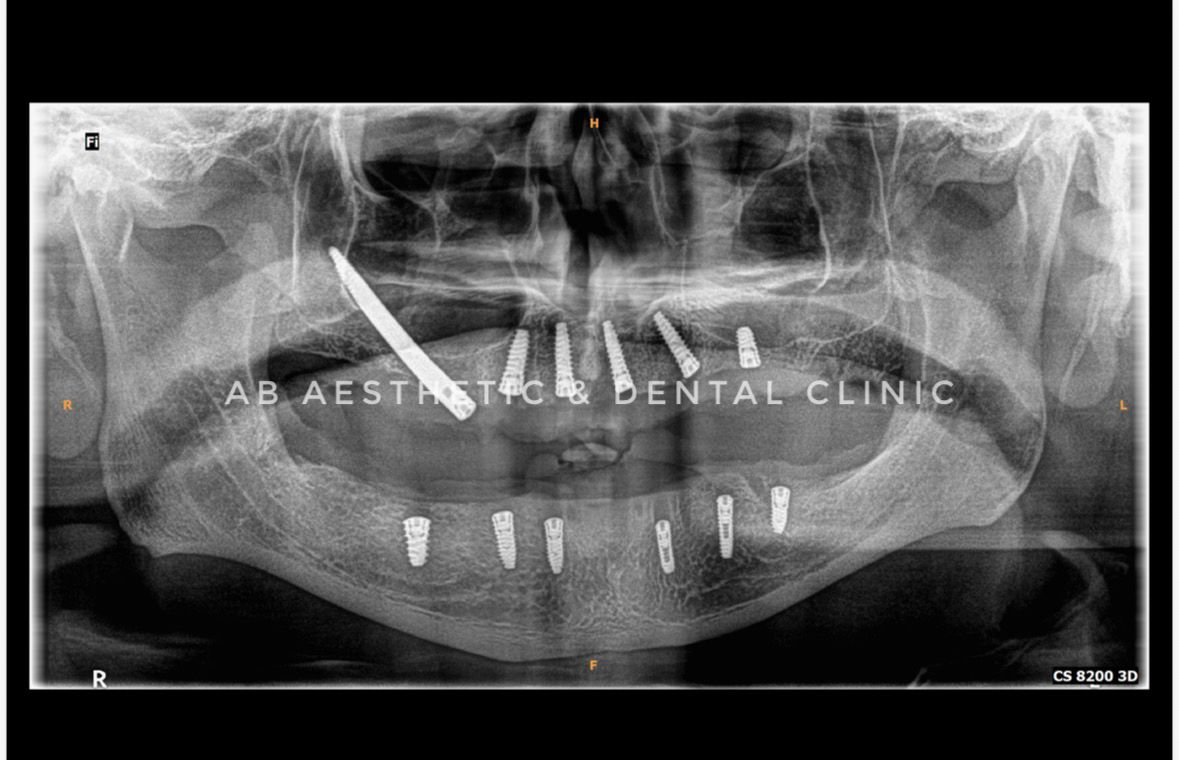

Zygomatic implants are an advanced solution for patients with significant bone loss in the upper jaw. Unlike traditional implants that anchor in the jawbone, zygomatic implants are placed in the cheekbone, which provides exceptional stability and eliminates the need for bone grafting. This innovative approach allows patients who were once ineligible for conventional implants to enjoy strong, functional, and natural-looking smiles again — all in a shorter treatment time.

At AB Aesthetic and Dental Clinic, our expert team utilizes advanced imaging and digital planning to ensure the precise placement of zygomatic implants with maximum comfort and accuracy.